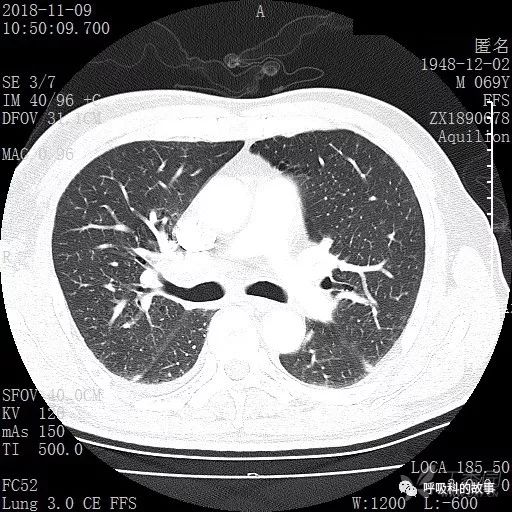

胸部增强CT示右肺门占位伴远端阻塞性肺炎,纵膈、右肺门、右侧颈根部、右侧腋下及肝门部肿大淋巴结。两侧胸腔少量积液。

肺窗CT